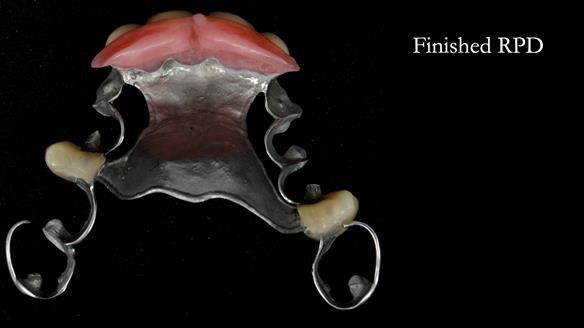

This is one of those cases that reminds me why I love removable prosthodontics. Pam was an absolute joy to treat — we were on the same page throughout. Her old upper flexible denture was loose, uncomfortable, and unaesthetic. We replaced it with a carefully designed metal-based upper partial denture/splint and new porcelain-bonded-to-zirconia (PBZ) crowns for the canines. The result is stable, comfortable, and natural-looking.

- Diagnosis and plan – Flexible upper denture ill-fitting with poor stability, retention, and appearance. Plan: metal-based upper partial denture/splint with lighter porcelain-bonded-to-zirconia crowns on UR3 and UL3.

- Fit and reviews – fit of the denture/splint and new crowns, followed by reviews to fine-tune comfort and function. Ongoing support and one-year warranty.

The result

- Better support for lips and lower face.

- Natural smile and improved chewing.

- Designed to protect remaining teeth.

- Future additions possible if needed.